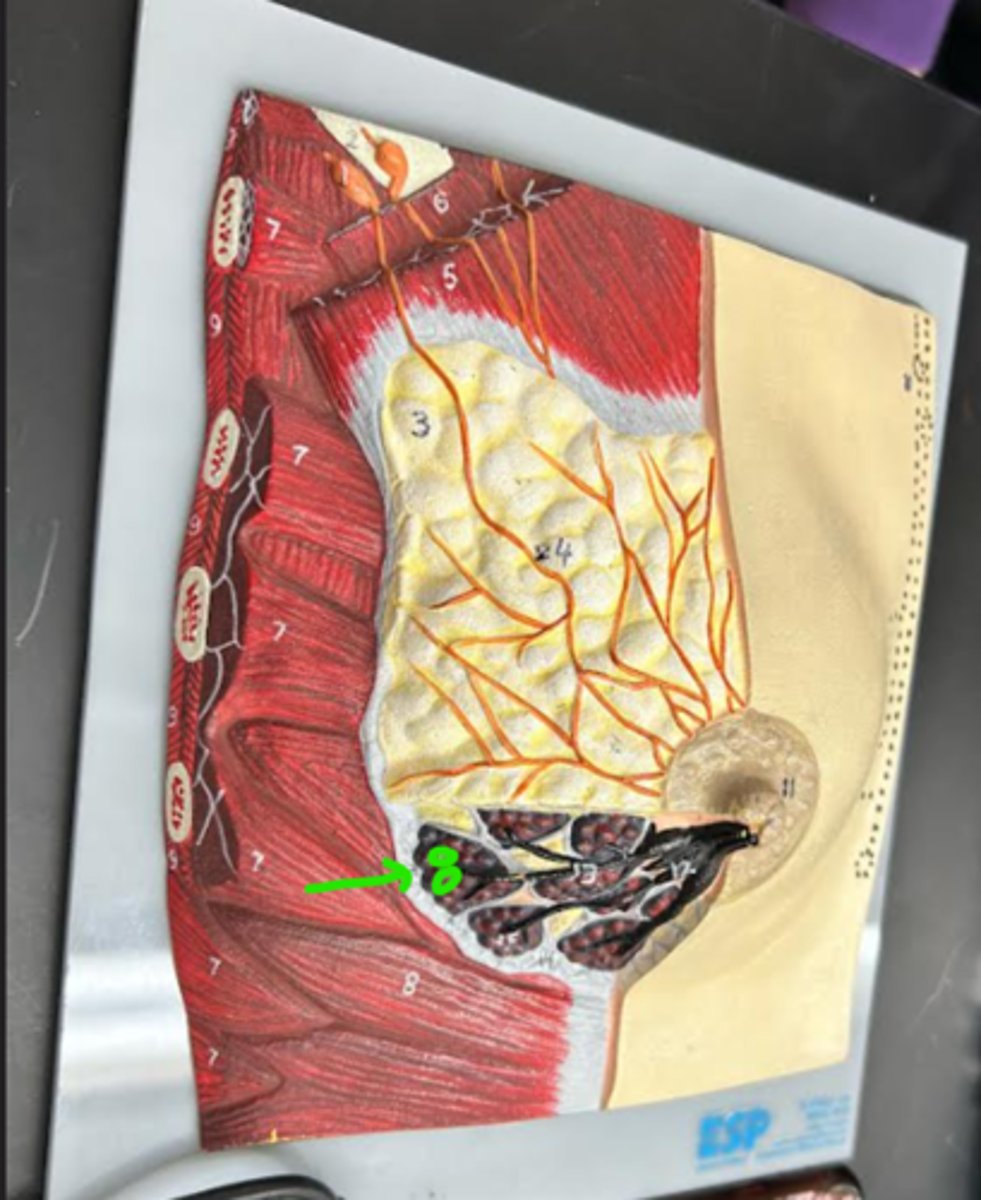

Breast

whole structure/ model

Mammary lobe

Mammary lobule